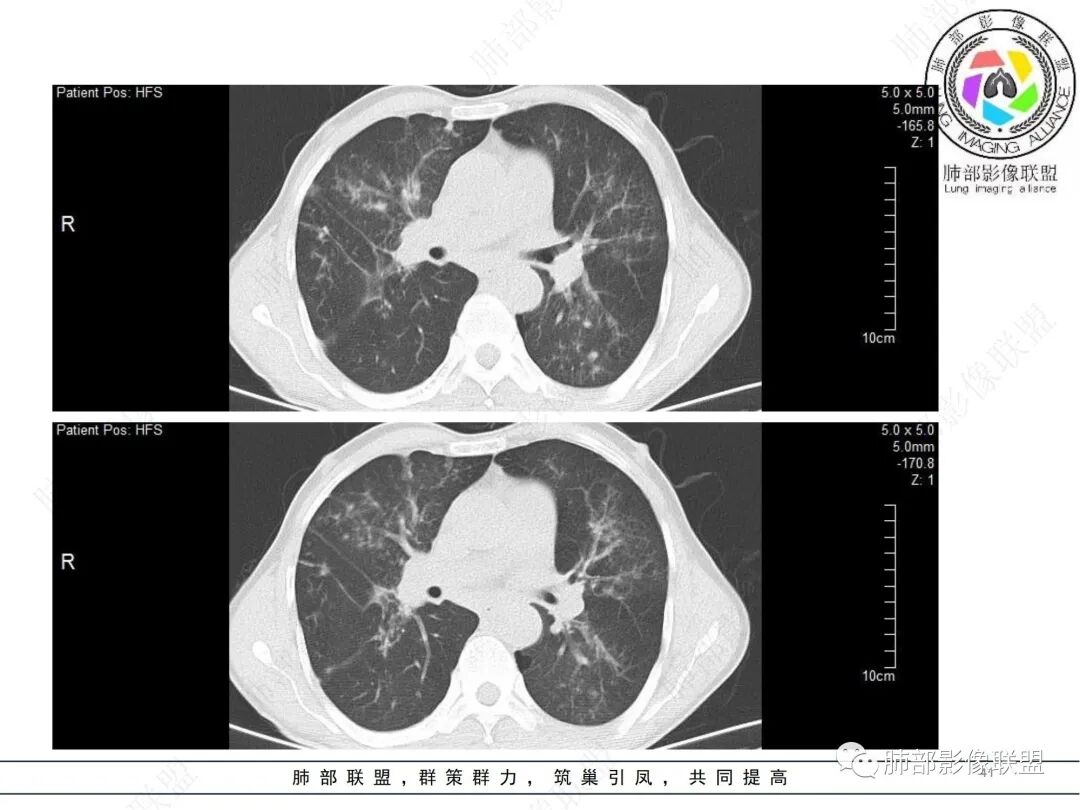

58岁男性,咳嗽胸闷3天,咳较多褐粘液痰,无发热。有2型糖尿病病史。白细胞与中性粒细胞升高。CRP升高。鳞状上皮细胞癌抗原轻度升高。结核T细胞免疫斑点实性阳性。肺炎支原体、衣原体IgG轻度升高。支气管镜显示支气管炎性改变、右肺下叶背段管腔狭窄。2.影像特点:

2022.6.24CT显示两肺弥漫性段、亚段支气管壁增厚(两肺各叶都累及),增厚的支气管壁外可见沿着支气管分布的渗出、实变影。另外远端肺内亦可见多发树芽影、结节影,其边界欠清晰。右肺下叶基底段局部胸膜下亦可见小斑片影,边界不清。2022.6.27CT显示两肺增厚的支气管壁外的渗出实变影明显增多、范围更广。远端肺内病灶亦增多、范围增大。部分位于胸膜下的病灶可见侧向融合趋势。3.病例分析: